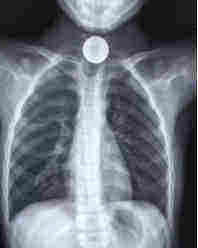

到医院后主要是排查胸部正侧位和腹部立位片,因为硬币为金属异物,所以在放射线下可以显出来,通过放射线片能够明确诊断,判断部位并且观察是否有硬币嵌顿和梗阻的情况。如果硬币在胃或食管内可以通过胃镜将其取出。如果硬币在肠道内并有嵌顿,甚至引起引起周围组织水肿及梗阻的情况,需要通过肠镜取出。